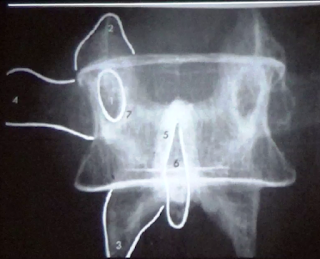

En la imagen de abajo logramos ver los siguientes

detalles anatómicos:

2 apófisis articular superior

3 apófisis transversa

5 apófisis espinosa

6 apófisis articular superior

7 espacio intervertebral

Algunas veces también puede verse la interlinea

articular de la articulación interapofisiaria.

OBSERVACIÓN: el agujero de conjunción está

limitado hacia adelante por el espacio intervertebral, hacia arriba por el piso

de los pedículos, hacia atrás por la apófisis articular superior e inferior y

hacia abajo por el techo de los pedículos de la vértebra adyacente.